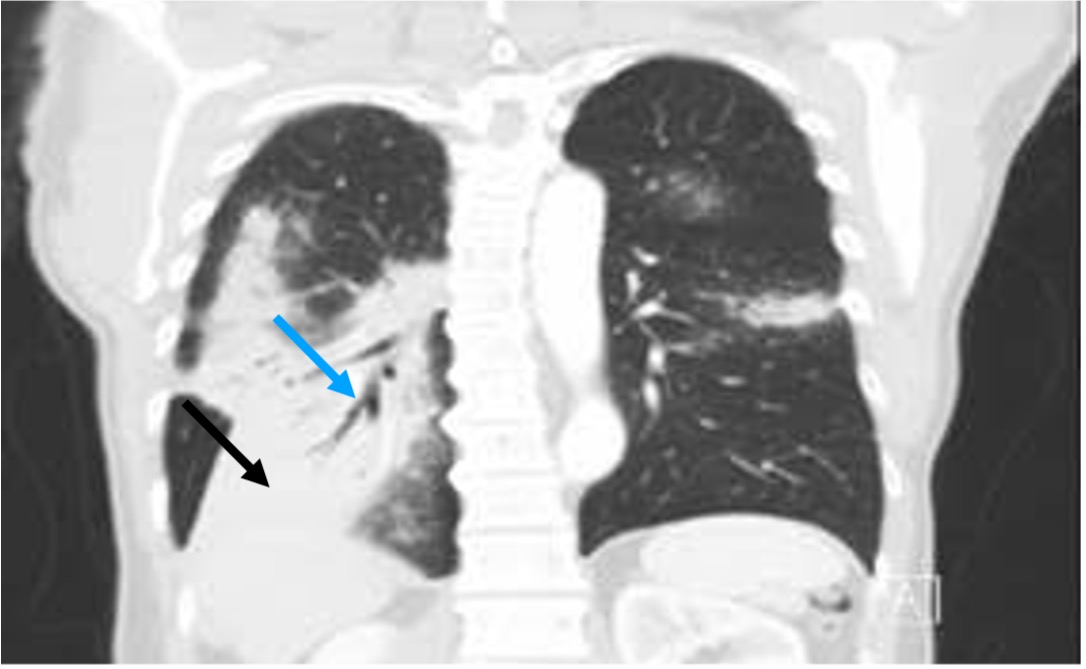

From pubs.rsna.org

Spectrum of CT Findings in Thoracic Extranodal NonHodgkin Lymphoma Chest X Ray For Lymphoma To look for possible signs of lymphoma coming back after treatment; To look for possible signs of cancer coming. Findings on a chest x. To help show if treatment is working; The amount of radiation used in most diagnostic tests is so small that it poses little risk to the patient. To help determine the stage (extent) of hodgkin lymphoma;. Chest X Ray For Lymphoma.

Mediastinal Masses in Children RadiologicPathologic Correlation Chest X Ray For Lymphoma Findings on a chest x. The amount of radiation used in most diagnostic tests is so small that it poses little risk to the patient. To help determine the stage (extent) of hodgkin lymphoma; Lymphomas are classified according to the who classification of tumors of hematopoietic and lymphoid tissues based on cell of origin (e.g. To look for possible signs. Chest X Ray For Lymphoma.